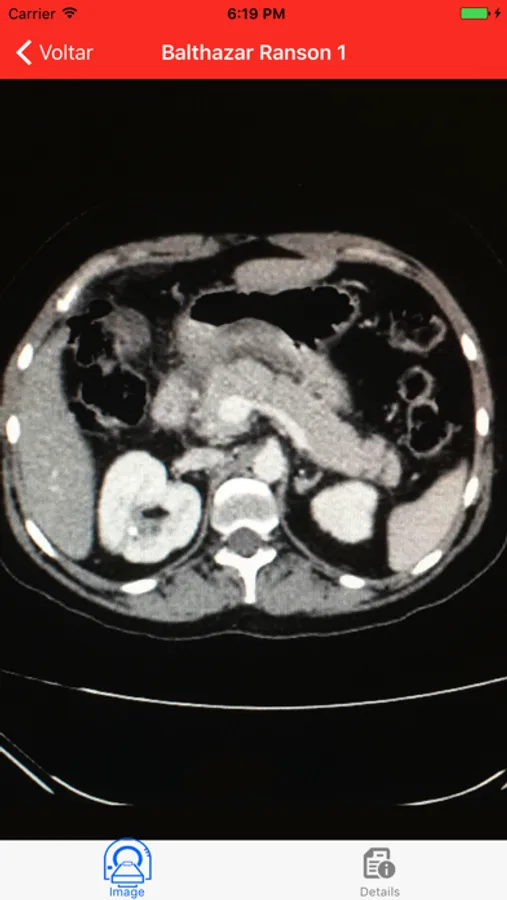

- Calculators major severity scores (Apache II, SOFA, Modified Marshall, Atlanta 2013, Severity determinants, Ranson, Balthazar-Ranson)

- CT Images